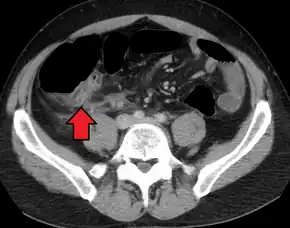

A CT scan demonstrating acute appendicitis (note the appendix has a diameter of 17.1 mm and there is surrounding fat stranding)

A fecalith marked by the arrow that has resulted in acute appendicitis.

Where it is readily available, computed tomography (CT) has become frequently used, especially in people whose diagnosis is not obvious on history and physical examination. Although some concerns about interpretation are identified, a 2019 Cochrane review found that sensitivity and specificity of CT for the diagnosis of acute appendicitis in adults was high.[59] Concerns about radiation tend to limit use of CT in pregnant women and children, especially with the increasingly widespread usage of MRI.[60][61]

The accurate diagnosis of appendicitis is multi-tiered, with the size of the appendix having the strongest positive predictive value, while indirect features can either increase or decrease sensitivity and specificity. A size of over 6 mm is both 95% sensitive and specific for appendicitis.[62]

However, because the appendix can be filled with fecal material, causing intraluminal distention, this criterion has shown limited utility in more recent meta-analyses.[63] This is as opposed to ultrasound, in which the wall of the appendix can be more easily distinguished from intraluminal feces. In such scenarios, ancillary features such as increased wall enhancement as compared to adjacent bowel and inflammation of the surrounding fat, or fat stranding, can be supportive of the diagnosis. However, their absence does not preclude it. In severe cases with perforation, an adjacent phlegmon or abscess can be seen. Dense fluid layering in the pelvis can also result, related to either pus or enteric spillage. When patients are thin or younger, the relative absence of fat can make the appendix and surrounding fat stranding difficult to see.[63]